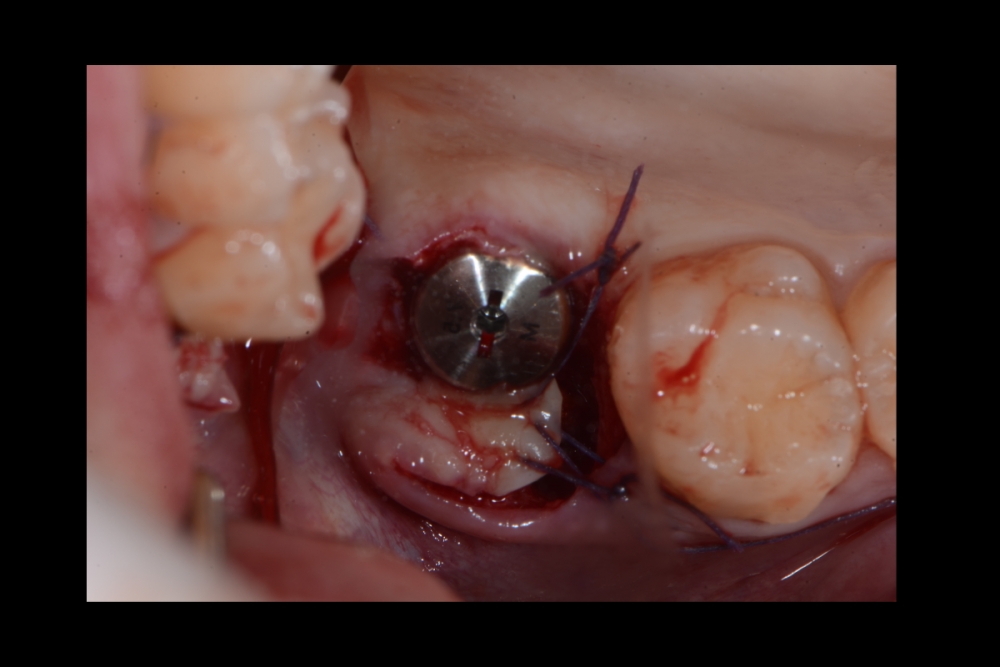

Карен Аванесов Опубликовано 20 сентября, 2021 Поделиться Опубликовано 20 сентября, 2021 (изменено) одномоментной установки имплантата, без вторжения в верхнечелюстной синус, регионарная мягкотканная пластика, выгодная ортопедическая ангуляция, не выгодной небной лунки. Пустоты заполнены губкой дигестол, дополнительная герметизация ликвидам. Мой только хирургический протокол, пациент реферативный. Время работы от удаления до имплантации 40 минут, ожидание до протезирования 3 месяца. Кейс посвящаю одноглазому и зеленому хулигану, любителю пива и девок, не знаю куда он делся, но пусть не грустит, все будет хорошо! Изменено 20 сентября, 2021 пользователем Карен Аванесов 10 1 1 Ссылка на комментарий

Карен Аванесов Опубликовано 25 сентября, 2021 Автор Поделиться Опубликовано 25 сентября, 2021 22.09.2021 в 18:52, сирена сказал: Ок) Бум ждать. А длина импланта какая? 10х4.5 1 Ссылка на комментарий